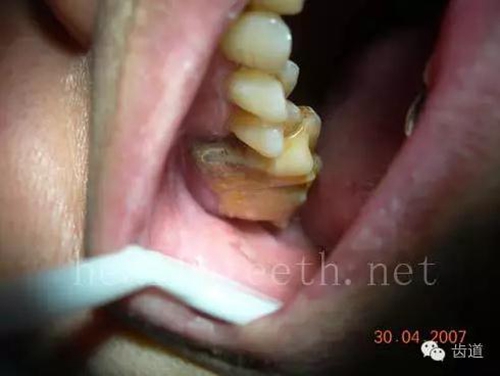

九、關(guān)于智齒(第八顆牙)

四顆長不出來的智齒

80.jpg

智齒反復(fù)發(fā)炎造成的頰瘺,膿腫切開引流后面部會留疤